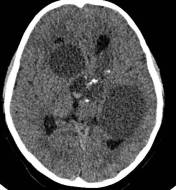

病例1:患儿男性,9岁。因反复出现意识丧失、视力下降半年收入院。入院后CT及 MRI显示颅内有形态不规则、“超大型”的颅咽管瘤,最大径约10厘米,见图1、图2。

图1.术前CT显示典型的囊性颅咽管瘤

图2.术前MRI

白色箭头指示肿瘤下极达枕大孔区